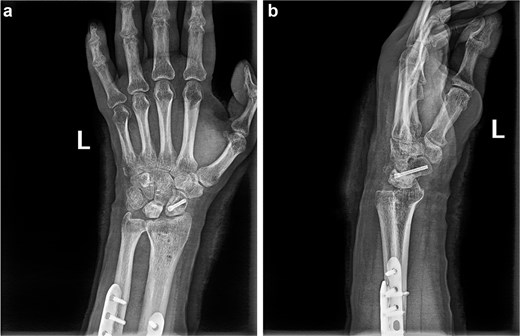

(a and b) Anterior and lateral views of the wrist joint after 6-month follow-up.